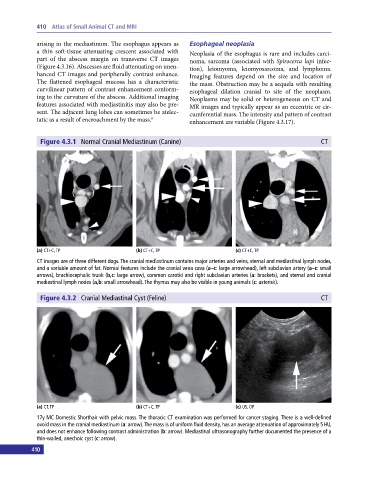

Figure 4.3.1 Normal Cranial Mediastinum (Canine) CT

(a) CT+C, TP (b) CT+C, TP (c) CT+C, TP

CT images are of three different dogs. The cranial mediastinum contains major arteries and veins, sternal and mediastinal lymph nodes,

and a variable amount of fat. Normal features include the cranial vena cava (a–c: large arrowhead), left subclavian artery (a–c: small

arrows), brachiocephalic trunk (b,c: large arrow), common carotid and right subclavian arteries (a: brackets), and sternal and cranial

mediastinal lymph nodes (a,b: small arrowhead). The thymus may also be visible in young animals (c: asterisk).

Figure 4.3.2 Cranial Mediastinal Cyst (Feline) CT

(a) CT, TP (b) CT+C, TP (c) US, OP

17y MC Domestic Shorthair with pelvic mass. The thoracic CT examination was performed for cancer staging. There is a well‐defined

ovoid mass in the cranial mediastinum (a: arrow). The mass is of uniform fluid density, has an average attenuation of approximately 5 HU,

and does not enhance following contrast administration (b: arrow). Mediastinal ultrasonography further documented the presence of a

thin‐walled, anechoic cyst (c: arrow).